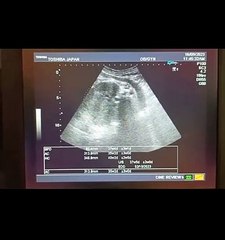

1 Male ♂️Gender at 37_38 Week with Difficult Sex Determination